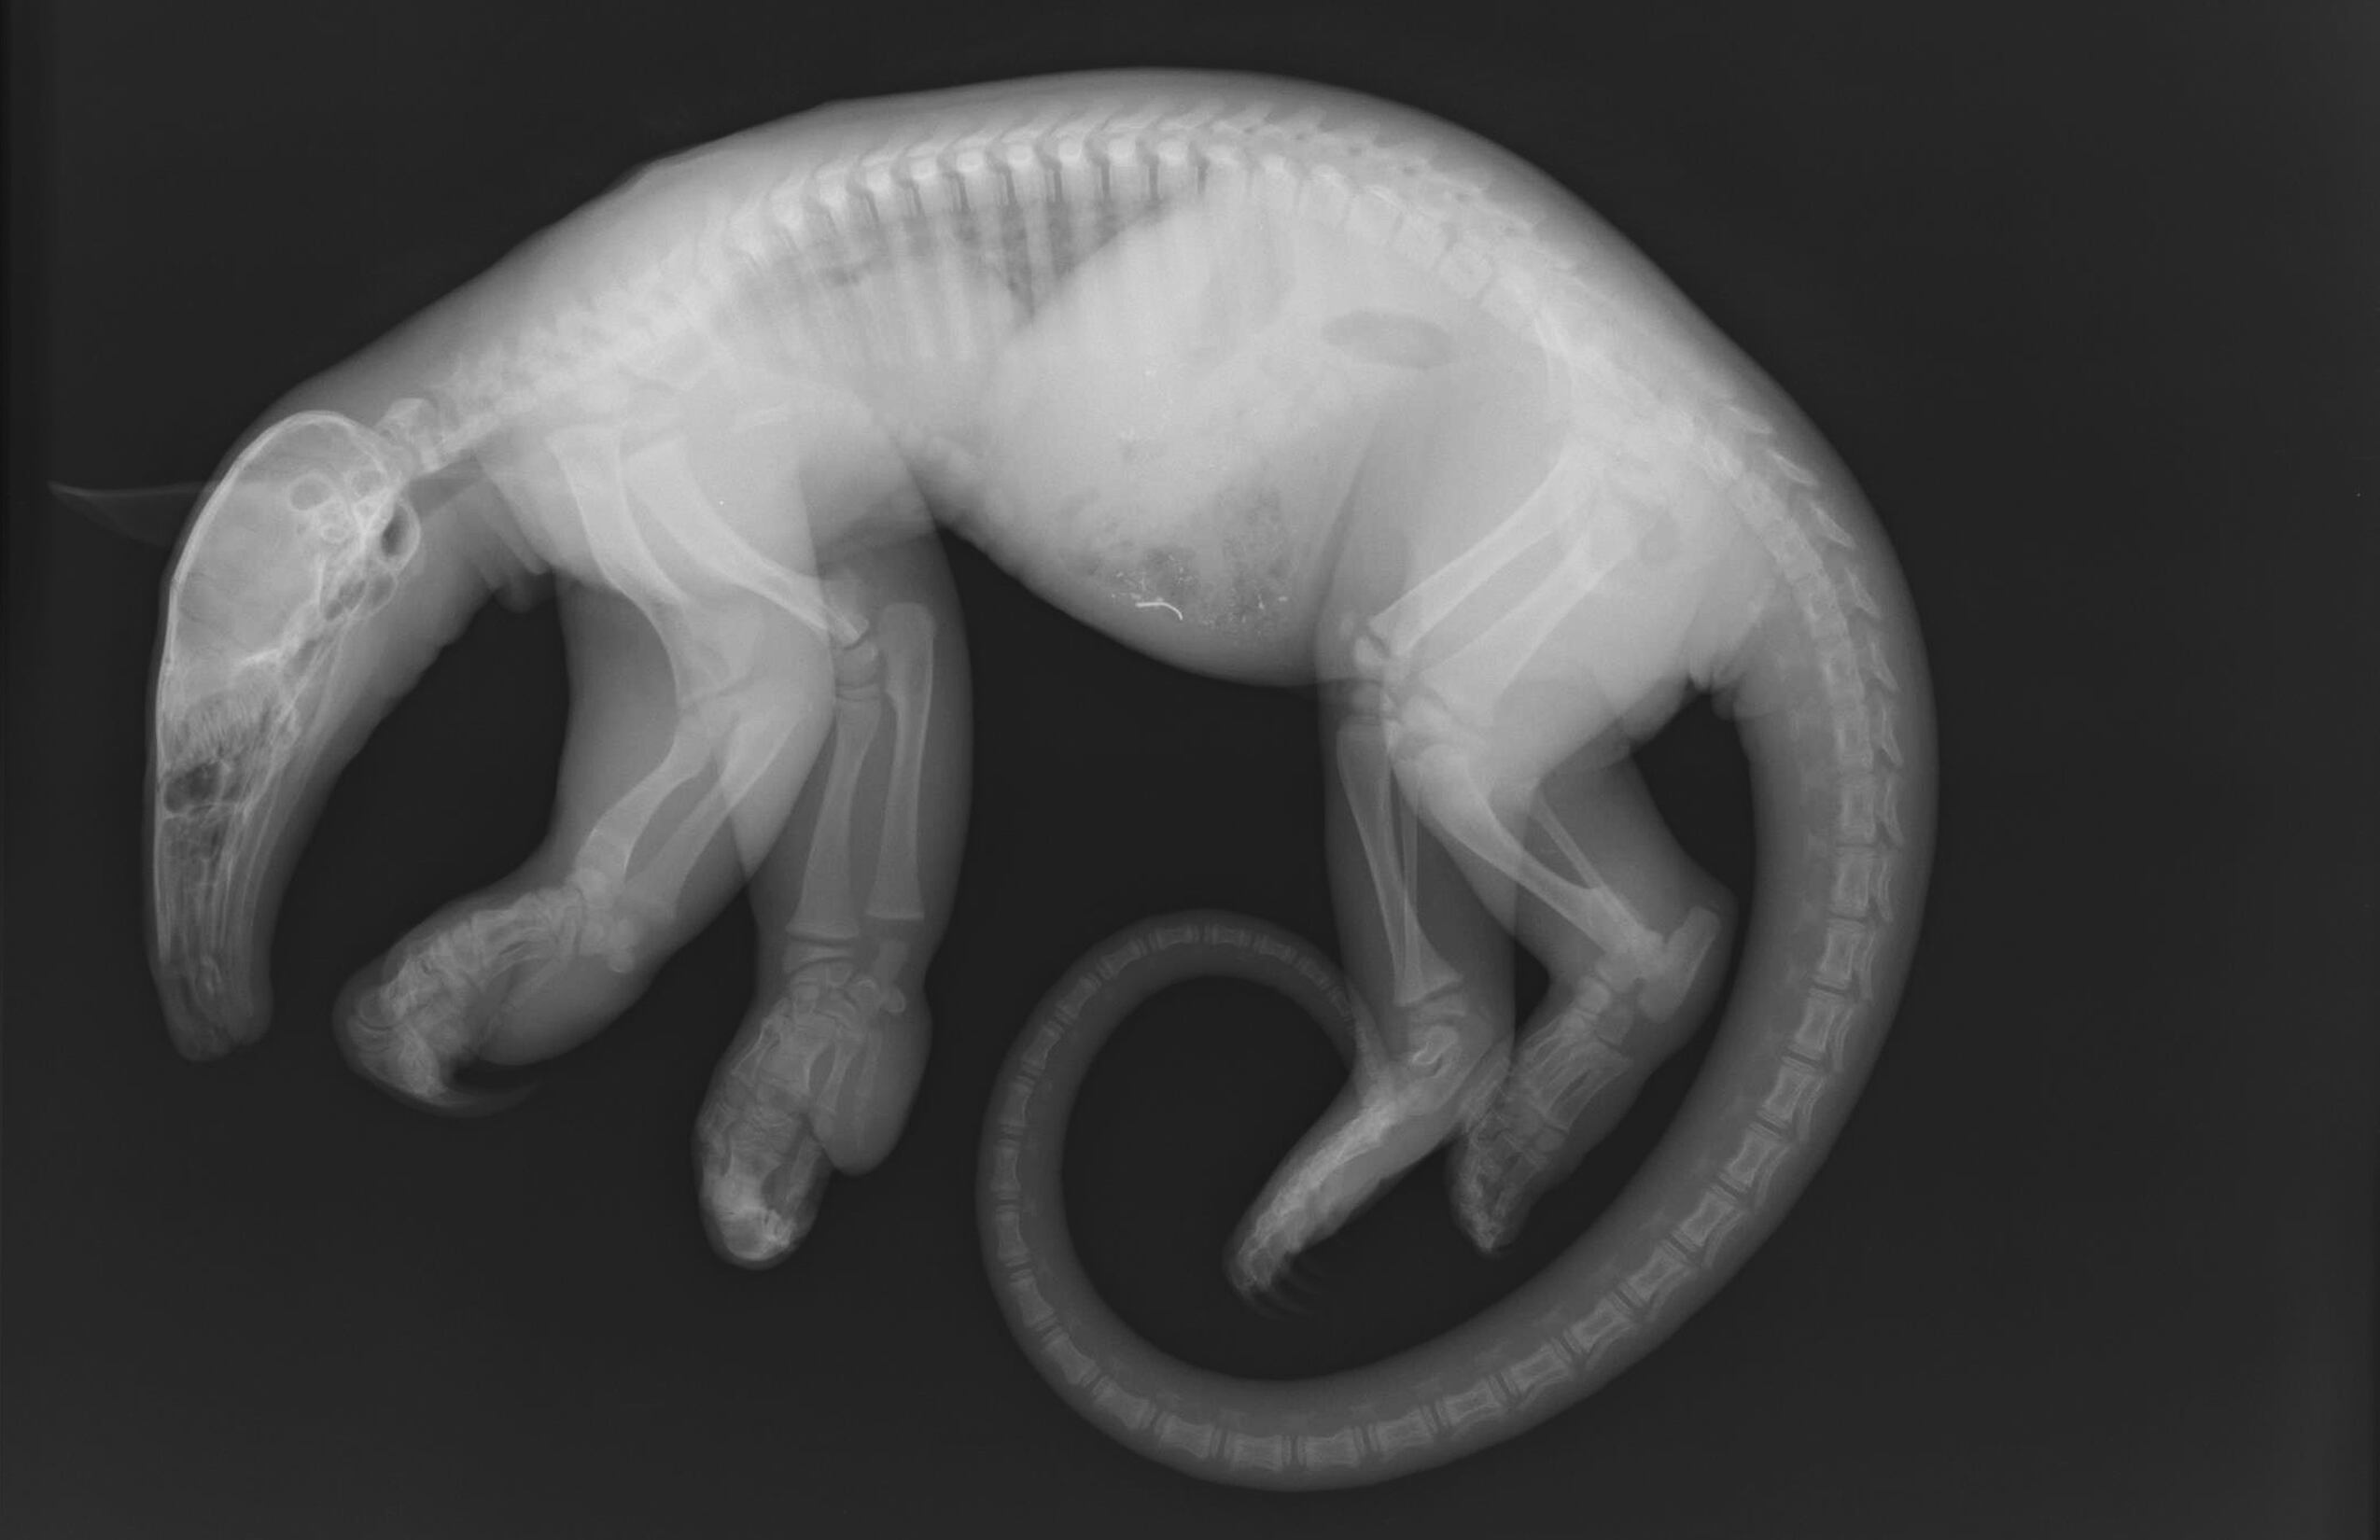

La radiografía de una boa enroscada, que a simple vista podría parecer serena, oculta una historia de maltrato. Llegó al santuario con heridas de machete, mientras que sus congéneres han aparecido con quemaduras, producto de haberse refugiado en el motor de un automóvil.